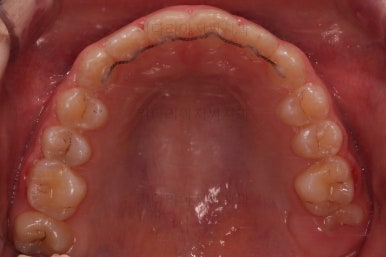

마무리를 해줍니다.

앞니 각도가 매우 좋아졌고요.(옥니 개선) 위 아래 앞니가 덮는 정도도 개선되었어요.(과개교합, 딥바이트)

엉성했던 어금니 맞물림도 매우 좋아졌어요.(앵글씨 2급 부정교합)

이상 일정부분의 성장교정과 치아교정을 통해 옥니, 과개교합, 앵글씨 2급 부정교합을 치료한 부산교정병원 사례였습니다.